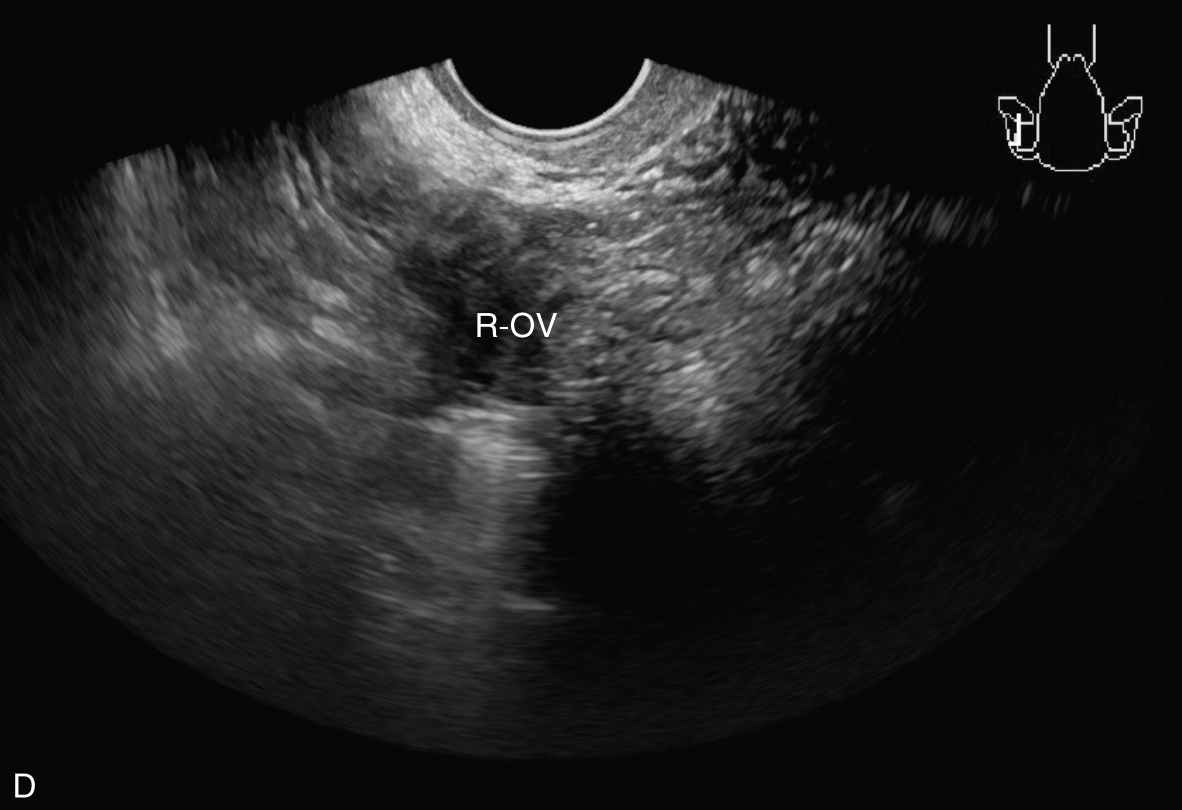

经阴道超声检查见图3-5-1。子宫后位,宫体大小约5.8cm×5.0cm×5.1cm,宫内膜厚约0.75cm(单层),内膜回声不均匀。宫腔未见分离。宫壁回声均匀。内膜内见多个囊性结节,较大者大小约0.5cm,内透声可。CDFI:未见异常血流信号。双侧附件区未见异常回声。盆腹腔未见明显积液。超声检查结果:宫内膜增厚伴回声不均匀。

图3-5-1 常规超声声像图

A.后位子宫的矢状切面(经阴道),子宫内膜增厚,单层厚约0.75cm,内见多个小暗区;B.后位子宫的横断面(经阴道);C.后位子宫的矢状切面(经阴道),彩色多普勒能量图超声检查显示子宫未探及明显血流信号;D.右卵巢;E.左卵巢。UT:子宫;EN:子宫内膜;R-OV:右卵巢;L-OV:左卵巢。